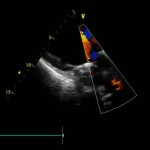

Дуплексное сканирование сосудов – современный метод диагностики заболеваний сосудов с использованием УЗИ, совмещенного с допплерографией.

Дуплексное сканирование сосудов позволяет оценить состояние стенок сосудов, просвета сосудов, обнаружить бляшки, стенозы (сужения), деформации хода и врожденные аномалии развития сосудов (гипоплазии, аневризмы). Данный способ диагностики позволяет также измерить скорость кровотока в любой точке сосудистого русла.

Дуплексное сканирование используется для определения нарушений кровотока в аорте, сосудах внутренних органов, головного мозга, шеи, глаз, верхних и нижних конечностей и т.д.

Дуплексное сканирование сосудов позволяет диагностировать сердечно-сосудистые и неврологические заболевания даже на ранних стадиях. Также в медицинском центре широко практикуется такой современный метод диагностических исследований, как денситометрия.